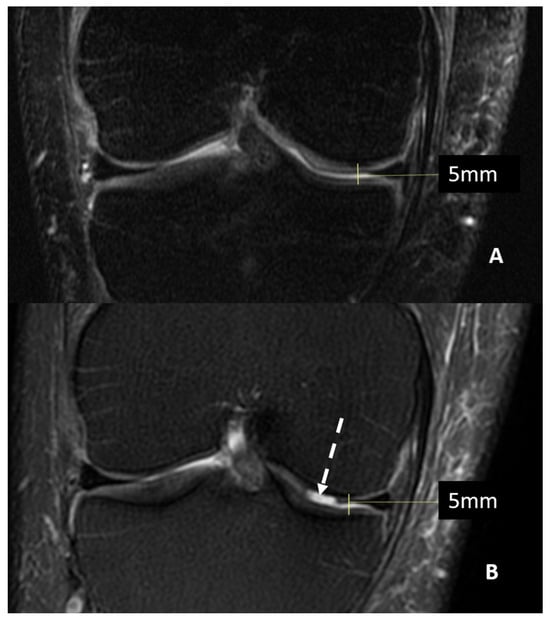

Magnetic Resonance Imaging (MRI) can offer valuable insight into inner structures and cartilage surfaces of the knee joint, with assessments that are both semi-quantitative and qualitative (Figure 1).

Figure 1.

MRI (T2w fat saturated coronal sequences) of a patient with suspected knee osteoarthritis at baseline (Panel A) and seven years later (Panel B). A progression of cartilage damage over time can be noted, especially at the medial femur condyle, where a large defect is detectable (arrow, Panel B), even if joint space thickness remains the same.